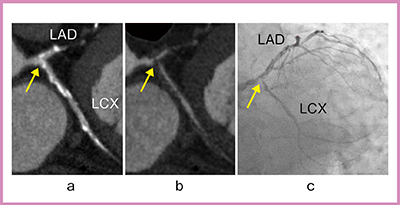

当クリニックでは,TBT法を応用した冠動脈サブトラクションを行っており,平均息止め時間は約13秒となっている。症例1の石灰化症例における造影CTでは,石灰化部分の狭窄を評価するのは困難であるが(図2 a),サブトラクションを行うとLADとLCXの分岐部に強度狭窄が認められ(図2 b↑),CAGでも同様の結果が得られた(図2 c↑)。

図2 症例1:石灰化症例

a:造影CT画像 b:冠動脈サブトラクションCT画像 c:CAG